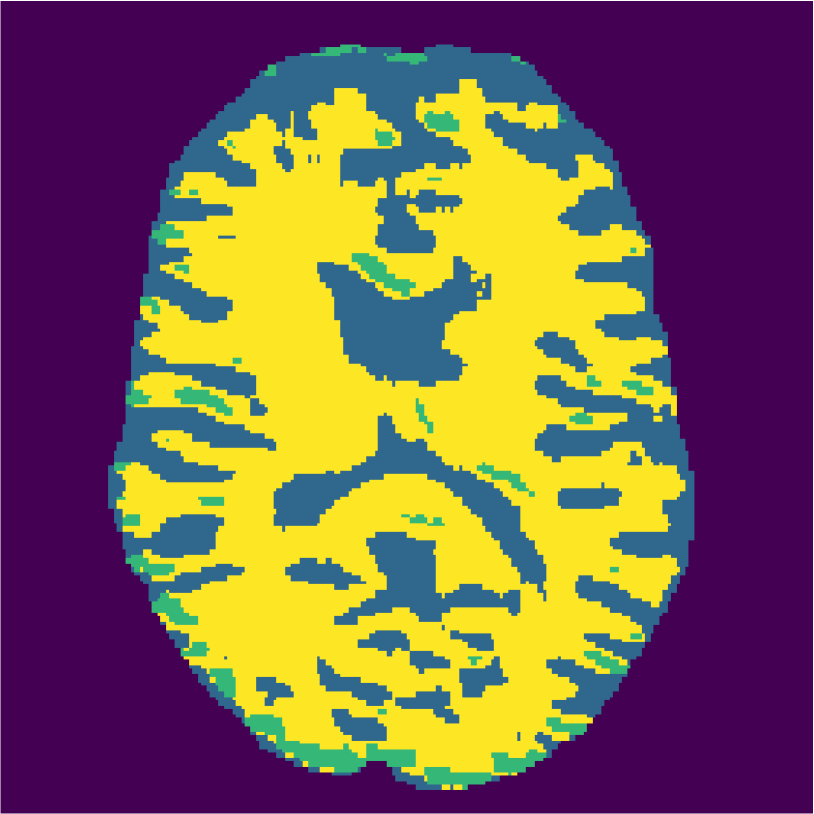

Figure 6 displays the manually selected patches and their position within the image. For both the source and target classifier, one target patch per tissue is insufficient to achieve good tissue classification performance (2 (top row): 0.631 and 0.613). However, the mrai-net classifier shows considerably better performance (0.223), using only one target patch per tissue. The proxy -distance also drops from near perfect separability (1.88) to near invariance (0.26). Randomly selecting (10 repeats) 1 target patch per tissue (Table 2 (bottom row)), shows worse performance of the mrai-net classifier, for both the classification error (0.250) as well as the -distance (0.41). Suggesting that purposive (information rich) sampling beats random sampling in this case.

Examples of the segmentation results on one of the target test images are shown in Figure 8 for experiment 2.1, Figure 9 for experiment 2.2, and Figure 10 for experiment 2.3. Examples are shown after using 1 target patch per tissue for training, and after using 100 target patches per tissue for training. The results show that only the mrai-net classifier is able to predict a segmentation that approaches the ground truth with only 1 target patch per tissue for training (error for experiment 2.1 = 0.269, experiment 2.2 = 0.403, experiment 2.3 = 0.320), while the source and target classifiers cannot (source error for experiment 2.1 = 0.667, experiment 2.2 = 0.653, experiment 2.3 = 0.435; target error for experiment 2.1: 0.591, experiment 2.2: 0.614, experiment 2.3 = 0.596). After using 100 patches the source and target classifiers can predict a gross segmentation of WM, GM and CSF (source error for experiment 2.1 = 0.213, experiment 2.2 = 0.384, experiment 2.3 = 0.363; target error for experiment 2.1: 0.205, experiment 2.2: 0.368, experiment 2.3 = 0.368), but the mrai-net classifier prediction shows more details and a lower tissue classification error (error for experiment 2.1 = 0.111, experiment 2.2 = 0.276, experiment 2.3 = 0.284).